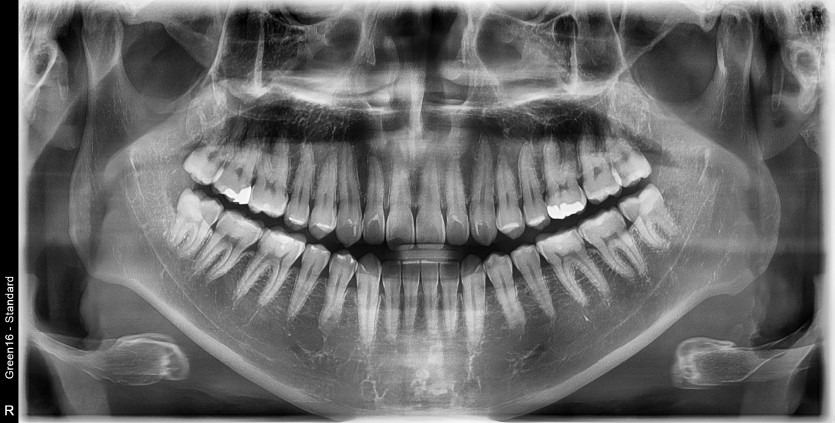

#28,38 사랑니 발치

구강 외과 전문의가 당일 발치했습니다.